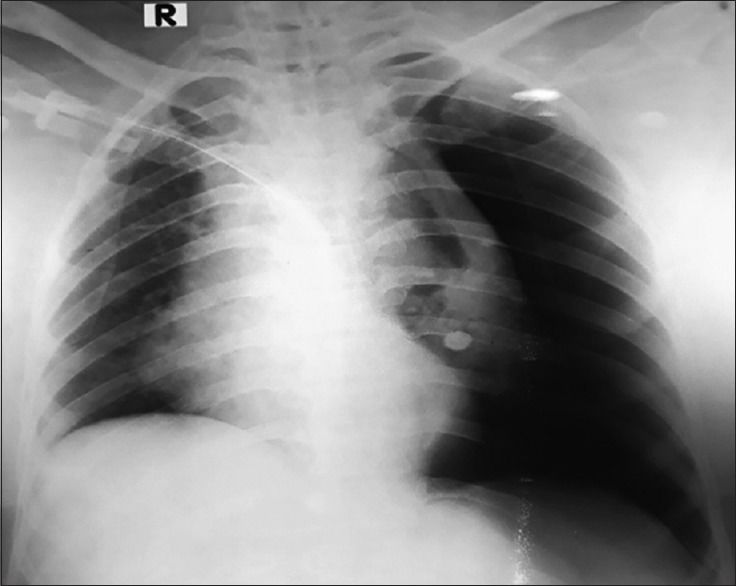

37岁男性因突发车祸入院,全身多处骨折及软组织挫伤,全身弥漫性疼痛感,无明显呼吸困难。刚入院时胸片检查除肋骨骨折外未见肺部损伤,心电图检查也正常。入院数分钟后患者突然出现左侧胸痛加剧,伴严重的呼吸困难。复查胸片可见明显的左侧气胸(见图3)

图3 左侧气胸